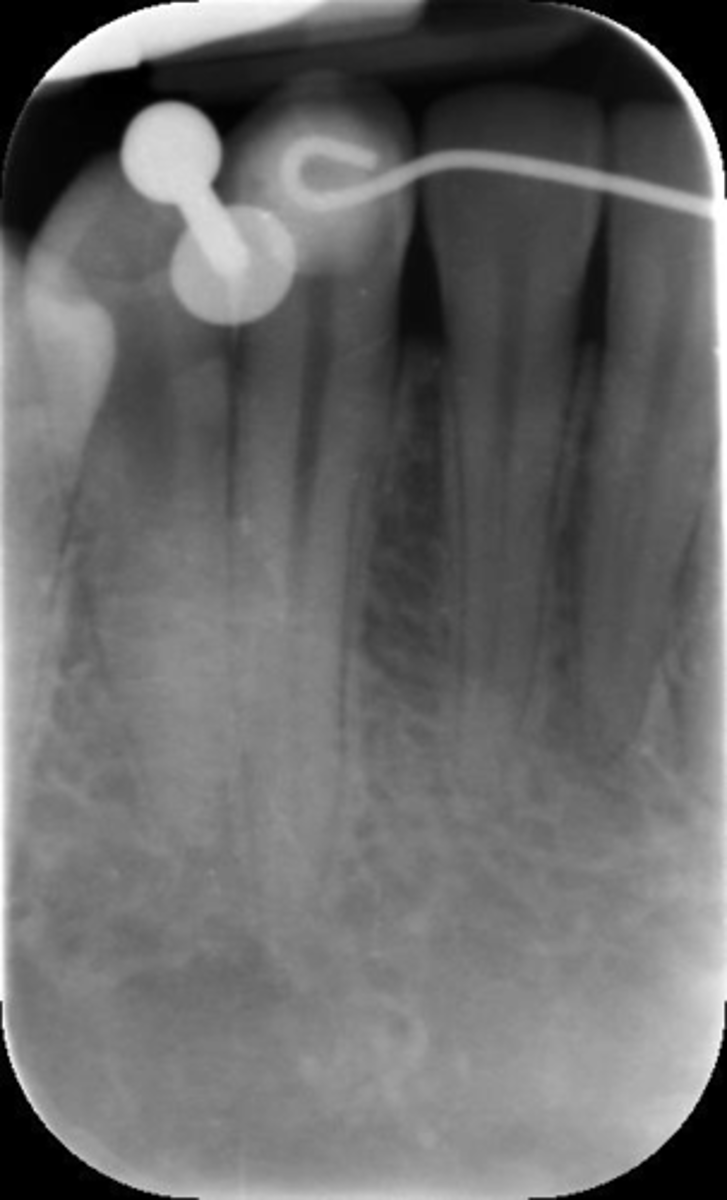

Rinn instrument bar, vertical angulation

What is this error?